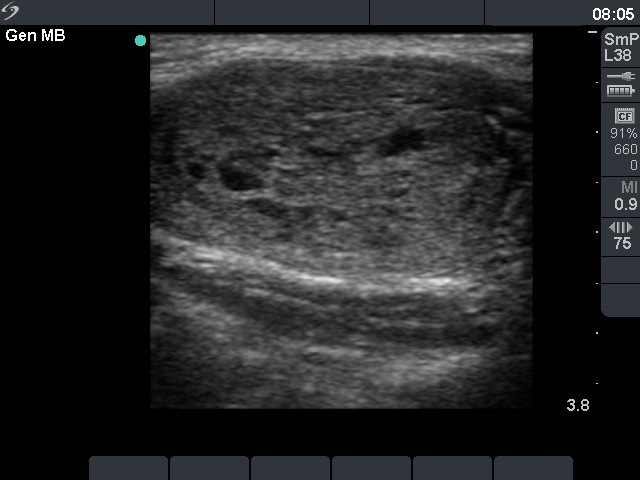

Characteristic ultrasound property - demonstration of a capsule only by Doppler mode

There are mainly two causes why not to demonstrate a halo sign on ultrasound. Firstly, the echostructure of the nodule may be identical with that of the capsule. This was the situation in the cases presented in the first 5 image pairs. Secondly, the capsule may be comprised and therefore we cannot find it on ultrasound. (See sixth image-pair.) In these situations the presence of a capsule may be evaluated by Doppler mode i.e. by the demonstration of vessels running in the capsule. There is a third possibility when a halo sign cannot be displayed, in the event of the so-called eggshell calcification. See next Table.